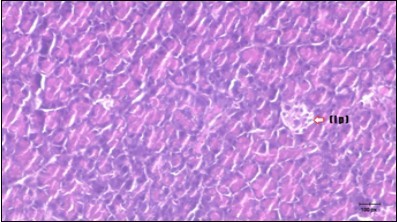

Pancreas Histopathological Observations

Histological examination of pancreas of the control rats showed normal sized islets of pancreas (Ip) compared to the diabetic rats which showed markedly atrophic islets of pancreas (I.p.) (Figure 8 and Figure 9). Pancreas of in groups (3) and (4) rats showed mild atrophic islets of pancreas (I.p.) with inflammatory cellular infiltrate (Figure 10 and Figure 11). The pancreas of rats in group (5) showed nearly normal islets of pancreas (I.p.) with few inflammatory cellular infiltrate (I.c.) (Figure 12).

Figure 9.Photomicrogragh of pancreas section of diabetic rat showing the markedly atrophic islets of Langerhans. (arrow) (H&E) (40X).

Figure 10.Photomicrogragh of pancreas section of treated rat with Fenugreek showing less improved islets of Langerhans with more cells (star). (H&E) (40X).